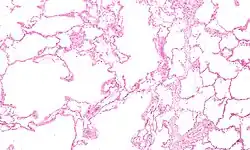

Pulmão com enfisema centrolobular característico do tabagismo. Este corte mostra múltiplas cavidades preenchidas por depósitos de carbono negro.

Microfotografia de um enfisema, em que se observa à esquerda grandes espaços vazios e à direita relativa conservação dos alvéolos.